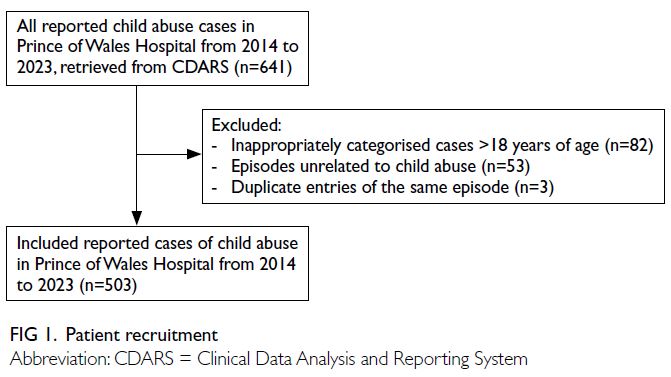

This retrospective study included all reported cases

of child abuse involving paediatric patients (aged

0-18 years) admitted to Prince of Wales Hospital,

a tertiary regional hospital in Hong Kong, over a 10-year period (from January 2014 to December

2023). All suspected or confirmed cases of child

abuse were identified from the Clinical Data Analysis

and Reporting System, an electronic health registry

managed by the Hospital Authority of Hong Kong.

The search utilised key terms under the International

Classification of Diseases, Ninth Revision coding,

including “Child maltreatment syndrome”, “Child

and adult battering and other maltreatment”, “Child

abuse”, and “Child maltreatment syndrome, shaken

infant syndrome”. Clinical records of all reported

cases were reviewed. Cases were excluded if they

were inappropriately categorised (aged >18 years),

erroneously reported as unrelated to child abuse, or

duplicate entries of the same episode (Fig 1).